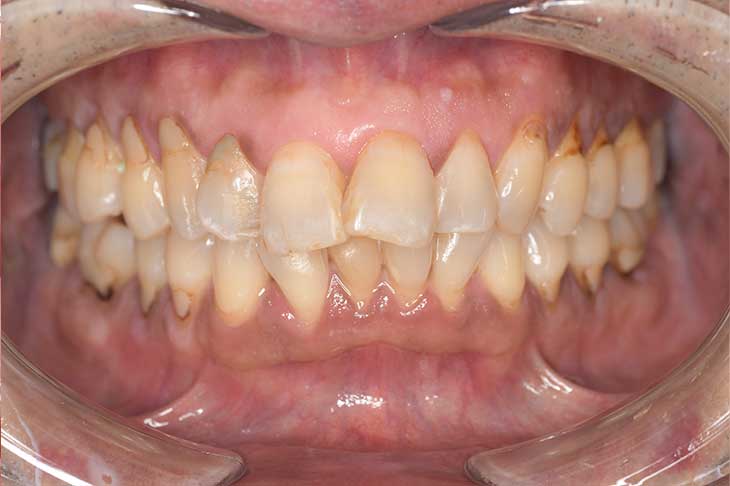

Before

After

基本情報

| 年齢・性別 | 52歳・女性 |

|---|---|

| 主訴 | クリーニングしたい |

| 治療内容 | スケーリング・PMTC |

| 治療期間 | 60分 |

| 治療費 | 約7,000円 |

| リスク・副作用 | 知覚過敏、歯肉退縮 |

| 治療方針 | 歯石とステインを除去して、今後は定期検診でのクリーニングと併せてガムピーリングやホワイトニングを行います。 |

| 担当者所見 | 歯肉の色素沈着が目立つため、ガムピーリングを行いながらホワイトニングを行うことをおすすめします。 |